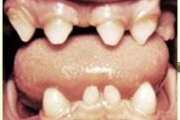

Koonilise kujuga lisahammas ülemiste tsentraalsete lõikehammaste vahel.

Suulaepoolt lõikunud koonilise kujuga lisahammas